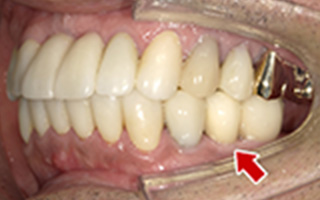

Before

After

| 60歳 男性 | 歯科大学病院 教授からの紹介 ご本人は産婦人科医 |

|---|---|

| 主訴 | 左下に歯が無くて食事がしずらい |

| 処置内容 | 2本インプラント埋入+再生処置 |

| 治療費用 | 下顎: 約80万円(税込) |

| 治療期間 | 下顎: 6ヶ月 |

| リスク | 術後の腫れ、痛み(ピークは3日後、1週間で軽減) |